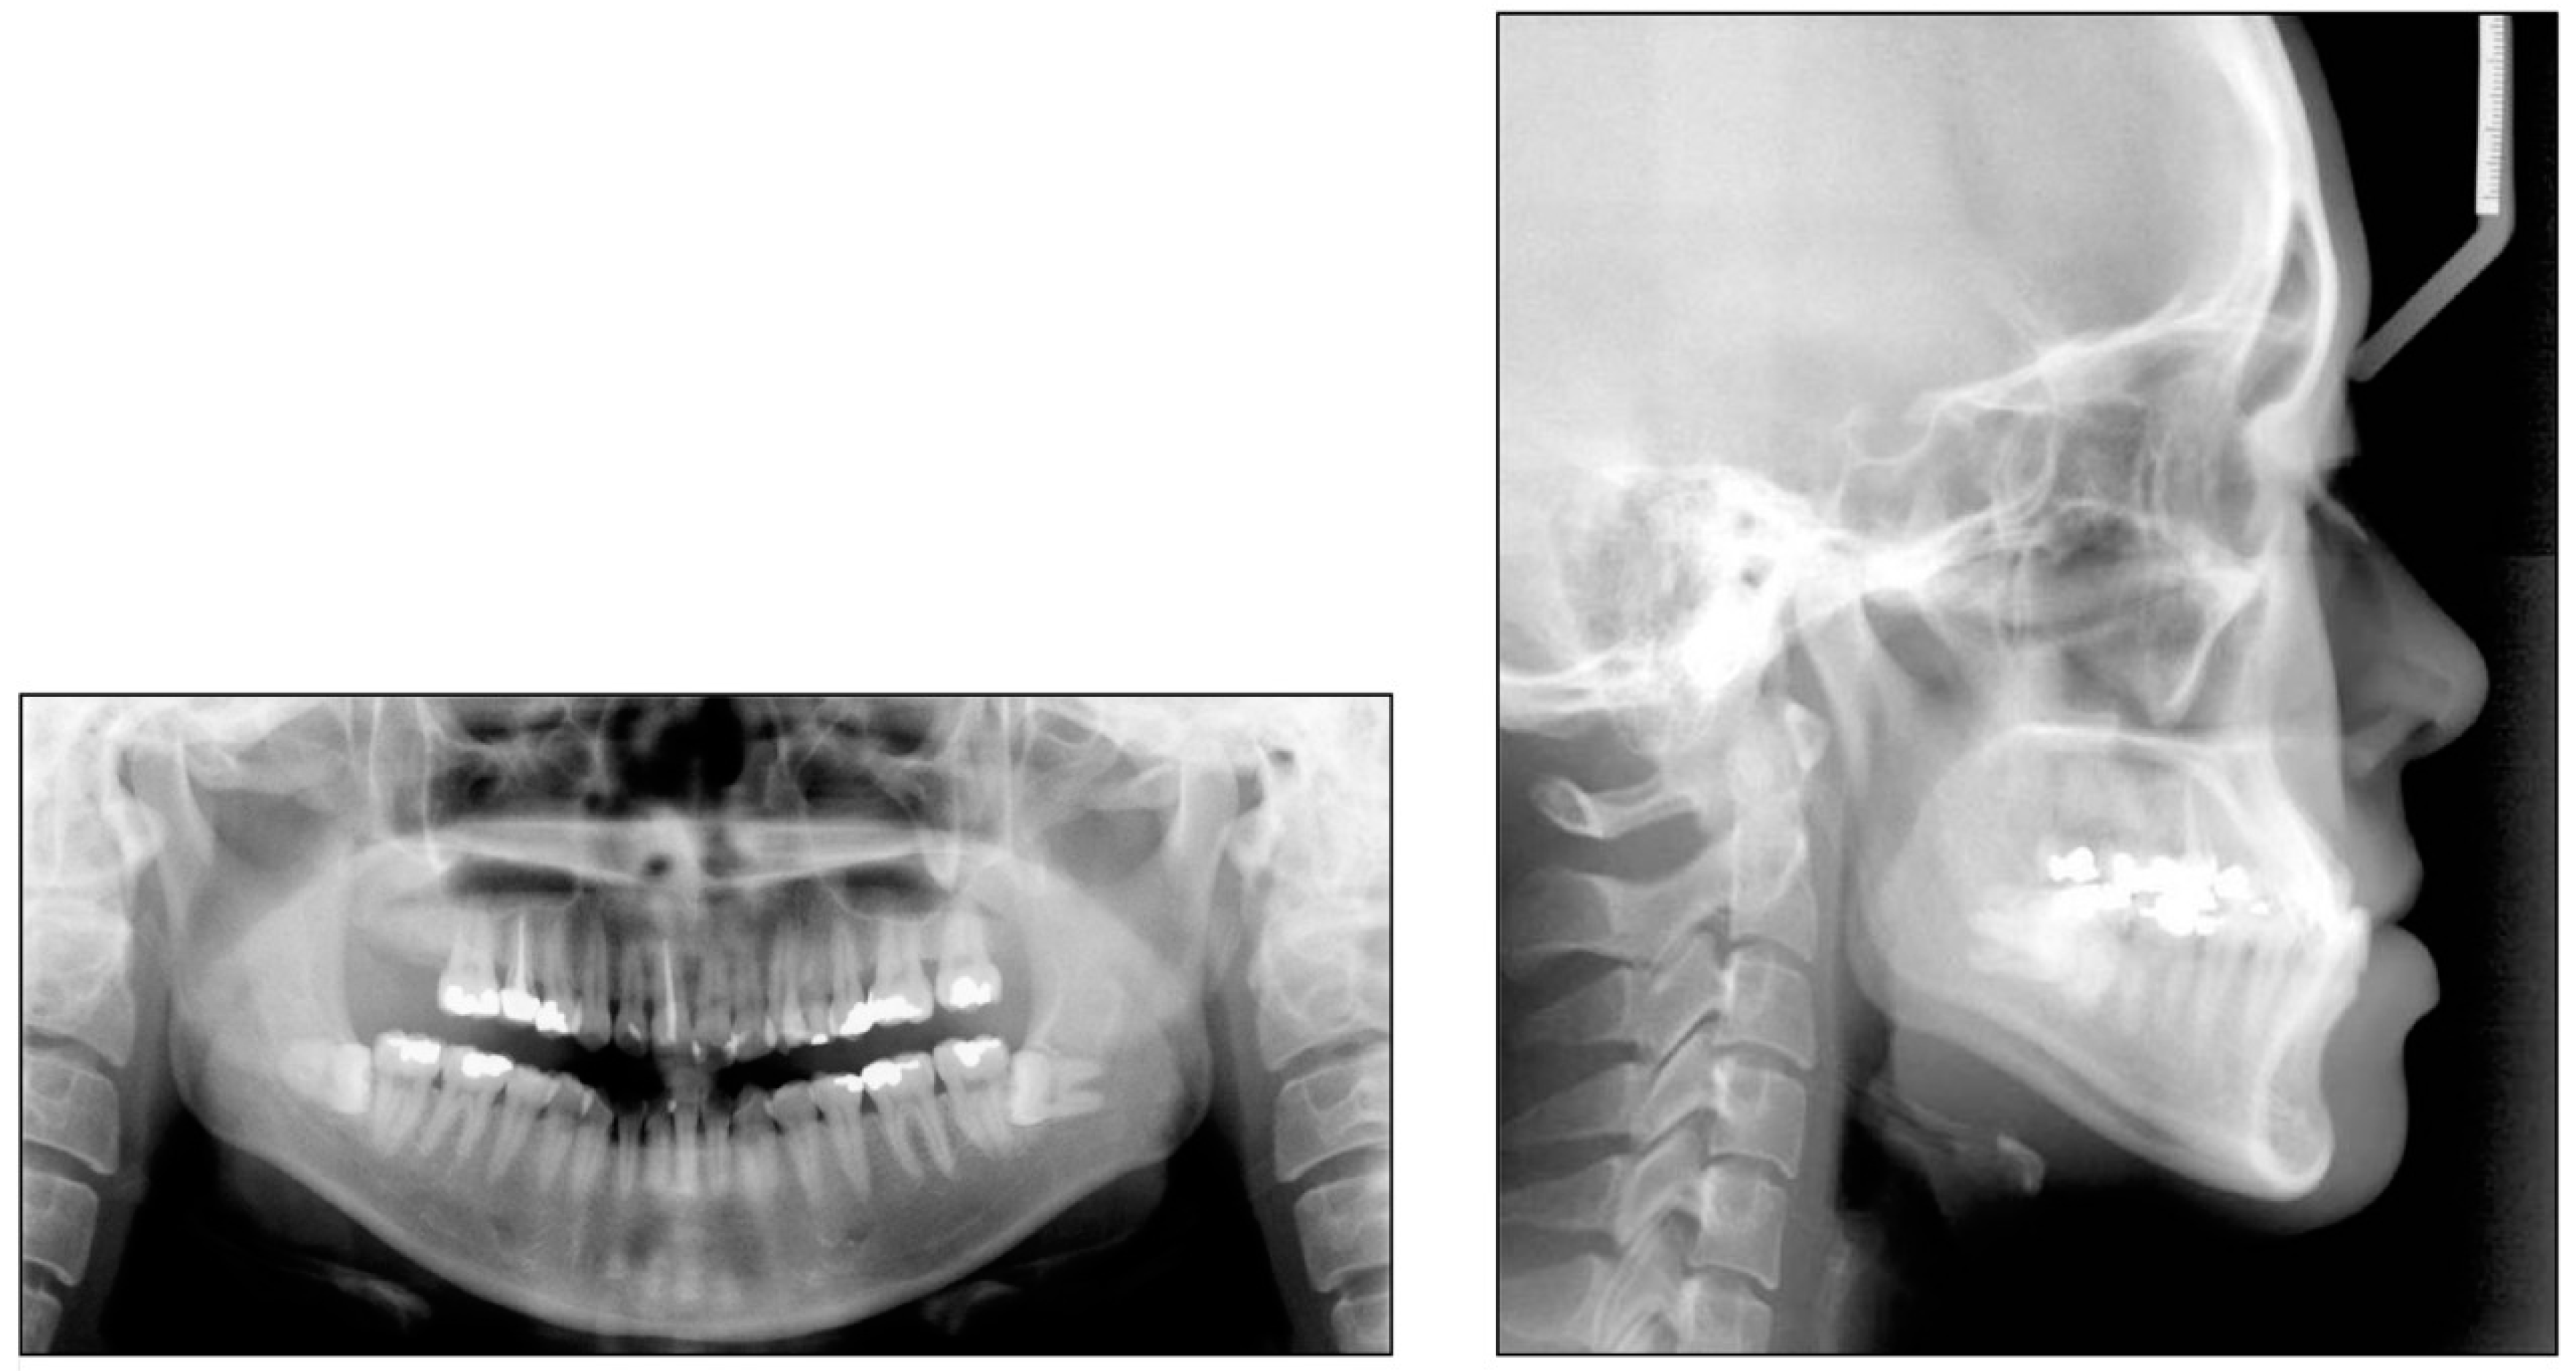

3.5. Treatment Results

4. Discussion